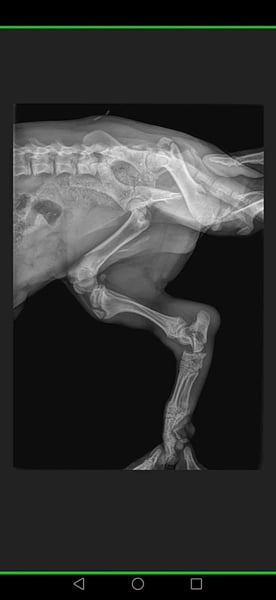

▪️wurde ausgesetzt auf der Straße mit einem gebrochenen Bein und einer riesengroßen Hernie.

▪️Der kleine Schatz wurde mit dieser Verletzung und mit der Hernie auf der Straße gefunden da war er ca. viereinhalb Monate.

Mit einer Hernie... Eine Luxation und ein Bruch am Bein

wurde er von einer Tierschützerin auf der Straße aufgegriffen.

Und der süße kleine Mann wurde operiert.

▪️Hernie operiert und Kastration durchgeführt.

▪️ Als die erste OP verheilt war, wurde PomPom nach vorheriger Absprache noch einige weitere Male unserem Tierarzt vorgestellt,

▪️um zu schauen ob man an seinem Beinchen noch operieren muss

oder ob man es so lässt.

Da man auch manchmal durch eine OP nichts verbessern,

sondern eher schlimmer machen kann.

⏯️Weil oft auch weniger mehr ist⏮️

Es wurde dann festgestellt der Bruch wächst sehr gut zusammen und der kleine Mann, wird vermutlich keine Einschränkungen mehr haben.

▪️Der komplizierte Bruch verheilte perfekt ohne weitere OP problemlos.

▪️ PomPom läuft heute ohne weitere gesundheitliche Einschränkungen.

▪️Er humpelt nicht, er ist ein süßer kleiner Feger, der nun endlich nach Hause möchte.